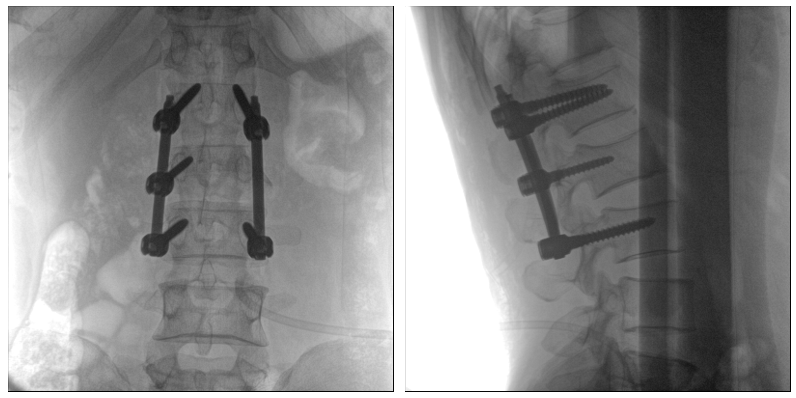

從下圖中可以看到二維影像能夠提供目標區域在某一個平面的重疊影像,雖然因為人體不同組織的密度差異,使得圖像具有較為豐富的信息量,但組織間的相互重疊還是會出現,諸如空間位置等眾多信息在影像中遺失或不可辨認的情況,影響了醫生對信息的收集與應用。

術中二維影像

而三維影像的MPR圖像組可以通過不同平面的切分,使成像區內更豐富的信息得以呈現。尤其是二維影像無法涉及的橫斷面,提供了另一個空間維度的信息量。

術中三維C臂影像

作為使用者,醫生在手術中雖然有術前的影像作為判定依據,但每一臺手術都具有獨特性,需要術中三維C臂影像提供的實時信息,作為術中診療操作的基礎。

術中三維C臂影像帶來的更加豐富的信息,可以作為醫生手術執行的判斷基礎,以及手術操作后實時的影像判斷依據,從而保障手術效果。

在既往的手術中可能會出現這樣的情況:術后在影像科CT檢查中發現某個手術效果需要調整,這時往往需要返臺、翻修等才能解決。而術中三維C臂提供的術中三維影像功能可以將這一步驟合并至手術流程中,有效地降低醫患雙方的風險,為手術保駕護航。